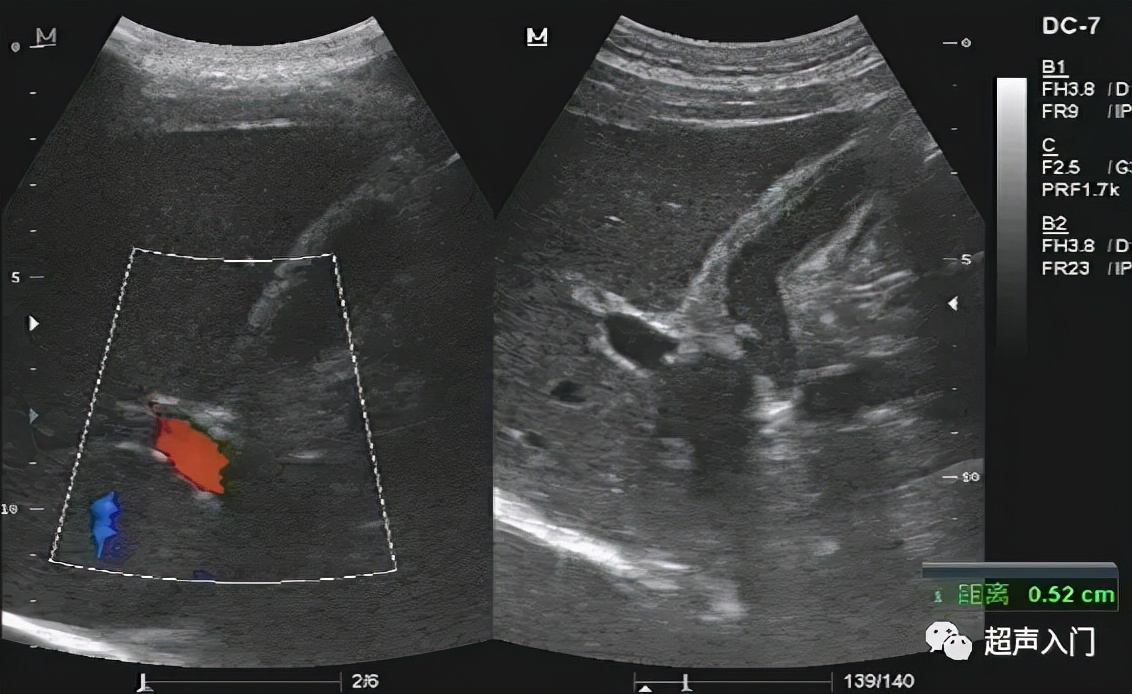

2、胆囊壁弥漫增厚,呈高回声,其间出现间断或连续的弱回声带,形成胆囊壁的“双边影”(double- laverecho)。

此征系浆膜下水肿、出血和炎性细胞浸润等改变所致。